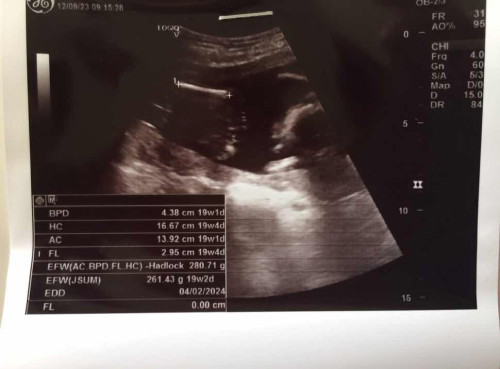

ฝั่งขวามือคือหน้าน้องใช่มั้ยคะ อิแม่ก็ดูไม่เป็น แต่คิดว่าน่าจะเป็นหน้าน้อง แล้วน้องกำลังอ้าปาก🤣 20วีค2วัน

น้องก้มหน้ายกมือขึ้น 2 ข้างค่ะ เส้นสีขาวที่หมอวัดคือกระดูกขา